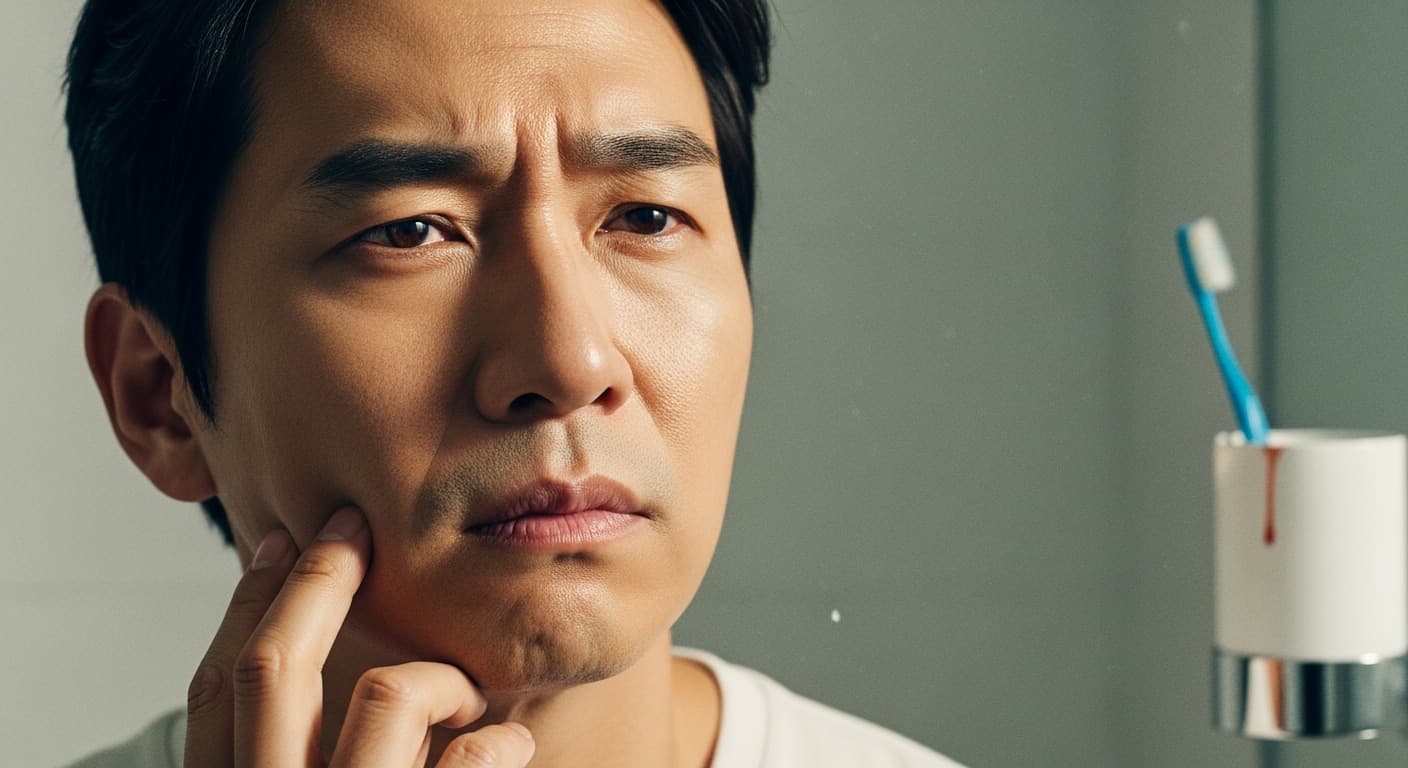

"아침에 일어났는데 잇몸에서 끈적한 피가 나고, 칫솔질할 때마다 시큰거리죠? 혹시 밥 먹다가 이가 흔들리는 느낌을 받으신 적은 없나요? 그저 나이가 들어서 그렇다고 생각하고 방치했다가는, 소중한 치아를 하나둘 잃을 수도 있어요. 오늘은 흔들리는 내 치아에 대한 우리 몸의 경고등, 그 진짜 이유를 함께 알아볼게요."